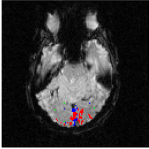

The Experience Based Cognition competition (EBC) (University of Pittsburgh, 2007) offers an opportunity to study complex responses to natural environments. The EBC datasets comprise three 20-minute runs (704 TRs in each run) of subjects interacting in an urban virtual reality environment. Subjects were audibly instructed to complete three search tasks in the environment: looking for weapons (but not tools) taking pictures of people with piercing (but not others), or picking up fruits (but not vegetables). The data was collected with a 3T EPI scanner (TR = s, xy dimension: , voxel size = mm, 34 slices with a thickness of mm). We analyze the second runs of subjects 14 and 13. For each subject, the matrix is composed of intra-cranial voxels at TRs. We first remove the non regionally specific variance captured by the first eigenmodes of a singular value decomposition of the dataset. We then compute using and . After embedding the dataset into four dimensions, we cluster the voxels. Figs. 18 and 20 display the datasets after embedding. Because we cannot display four dimensions, we show the projections of the dataset on three consecutive coordinates. All the coordinates contribute to the spread the dataset along elongated arms, which facilitates the clustering. Voxels that do not correspond to the background activity (the maroon cluster in Figs. 18 and 20) are superimposed on anatomically registered structural images and colored according to their cluster label (see Figs. 19 and 21). For both subjects, the clusters are connected regions (see Figs. 19 and 21), compactly organized around functional areas related to the processing of visual, and auditory stimuli (music, cellphone ringing, dog roaring) in the virtual environment. It is important to emphasize that our method never enforces any form of spatial proximity, and is purely based on functional connectivity.

For subject 14 (Fig. 19), the orange cluster corresponds to activation in the calcarine cortex associated with V1/V2 representations of the lower visual fields, while the light blue cluster corresponds to representations of the upper visual fields. Activation in lateral areas (visual motion areas, MT/V5) is also present, as well as activity in the posterior convexial cortex (area VP). The activation is predominantly in the right hemisphere. Interestingly, the two clusters located in the visual cortex (light blue and orange) have very similar and coordinates (see Fig. 18-left). The cyan cluster corresponds to activation in the right frontal gyrus (Broca area) associated with language comprehension. The yellow clusters are located in the right and left superior temporal gyri and medial temporal gyri (Wernicke area). These regions correlate with activation

in the auditory cortex and language areas. Finally, the dark blue cluster corresponds to activation in the prefrontal cortex. A very similar pattern of activity (Fig. 21) was obtained for subject 13. The blue and orange clusters, located in the calcarine cortex, correspond to V1 and V2 areas. Again, these two clusters, both located in the visual cortex, have similar and coordinates. The green cluster is located in the medial temporal gyrus (Wernicke area) and is associated with language processing.